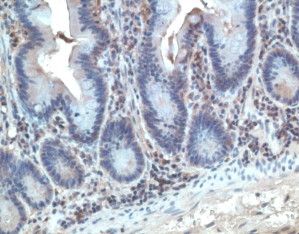

IHC-P analysis of human tonsil tissue using GTX23904 CCR10 antibody.